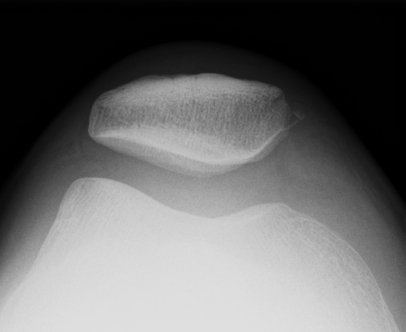

Lateral Xray

1. Assess Patella Alta

A. Blumensaat's line / Inaccurate

Knee flexed to 30o

- line should just touch inferior pole of patella

- pole above line - alta

- pole below line - baja